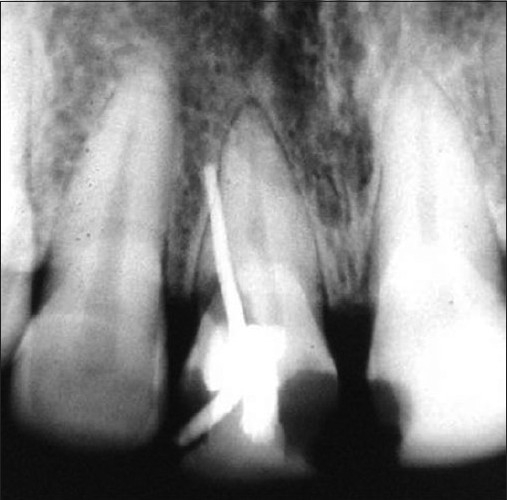

Radiographic evaluation of 37 showing widening of periodontal ligament

Radiographic evaluation of 37 showing widening of periodontal ligament What Is Pdl Widening The periodontal ligament, commonly known as the pdl, is a soft connective tissue between the inner wall of the alveolar socket and the roots of the teeth. The normal width of a periodontal ligament space should be 0.5 mm or less. The aim of this article is to review a group of lesions associated with periodontal ligament (pdl) widening. Increased. What Is Pdl Widening.